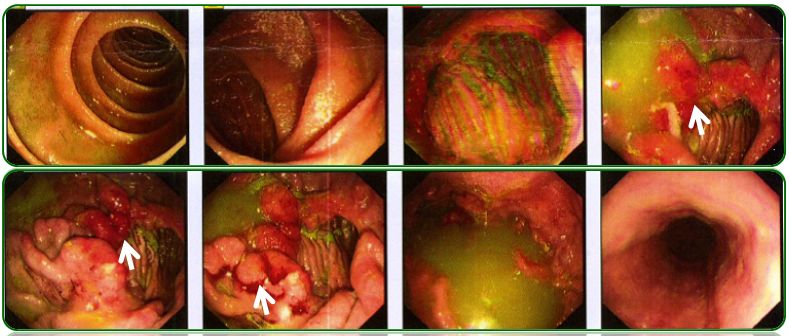

胃镜、肠镜未见异常,如图6;

图6 胃镜、肠镜检查

回归本例患者在门诊给予促进胃肠动力及补充消化酶治疗效果欠佳,因此行腹部彩超检查,提示腹腔积液,门诊收住院进一步检查。由于患者上腹部胀痛,进食后明显,查体剑突下轻压痛,毫无疑问胃镜检查必须做,腹腔积液患者也需要排除肠道肿瘤,因此肠镜也需要完善,所幸的是胃肠镜检查均未发现异常。